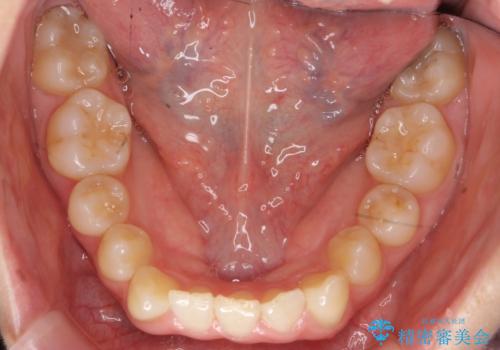

- 前歯のがたつきを主訴に来院。

下の前歯は生まれつき1本少ない状態でした。

左上の犬歯が入りきらずねじれており、かみ合わせもずれていました。

左上の小臼歯を1本抜いて治療しています。

前歯は内側に傾いており(ラビッティング)、過蓋咬合(深いかみ合わせ)を呈していました。

難しい治療でしたが綺麗に咬み合わせることができ、また前歯もしっかり当たるように治療できました。